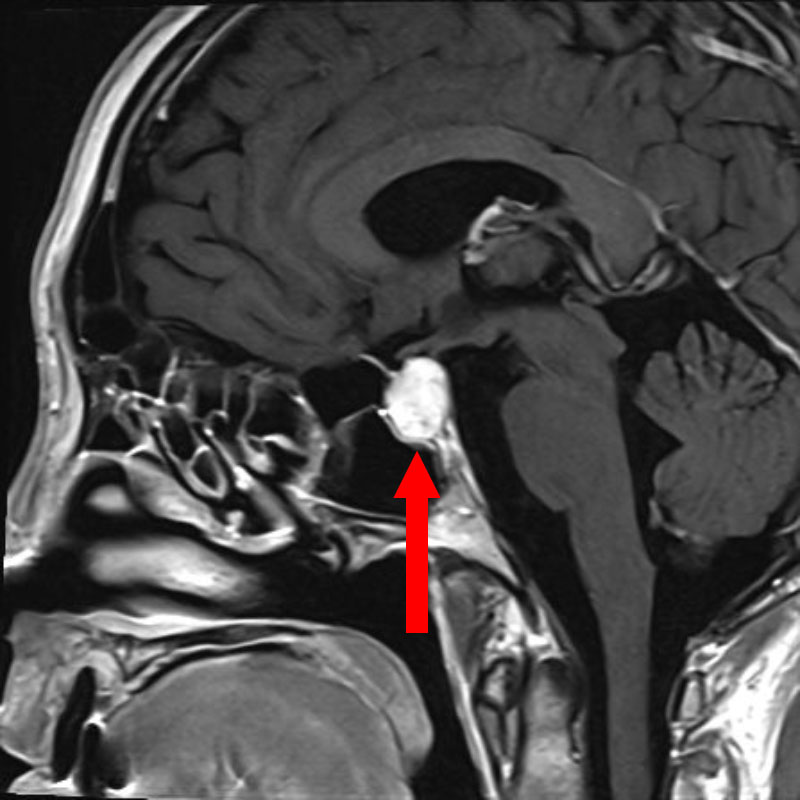

頭蓋咽頭腫

頭蓋内腫瘍摘出術

No.’25_96 手術前1

No.’25_96 手術前2